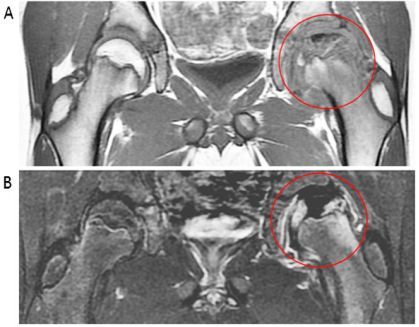

- 出现髋关节疼痛、活动受限(如抬腿困难)时,及时就医,通过X线、MRI明确分期,避免延误治疗。